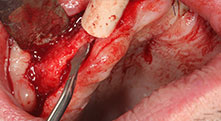

Bratu: Wir bevorzugen Knochenentnahmen von der Linea obliqua externa des posterioren Unterkiefers, nicht aus der interforaminalen Region. Nach der Weichgewebsinzision verwenden wir die neuen Sägen, um den Umfang der Knochenentnahme zu definieren. Wir erledigen damit in fast 80 Prozent der Fälle auch die gesamte Präparation. Zusätzlich verwenden wir eventuell andere Piezo-Instrumente und zuletzt einen Meißel, um den Block zu mobilisieren. Das ist für uns eine sehr effektive Operationstechnik.